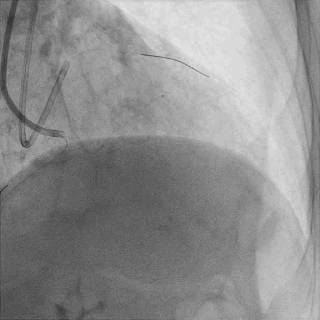

双侧造影,观察闭塞起始位置、长度、走行等

尝试通过RCA-圆锥支侧枝逆向开通LAD :

微导管辅助下,用SUOH03导丝尝试送入侧枝

经微导管TIP injection可见侧枝重度迂曲

侧枝重度迂曲,反复尝试未能通过